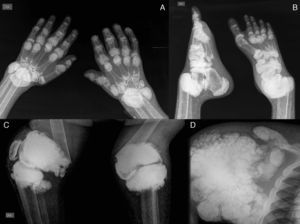

El patrón de afectación articular más común es una poliartritis u oligoartritis simétrica, aguda o crónica, con compromiso de las articulaciones metacarpofalángicas e interfalángicas proximales, con o sin tenosinovitis, junto con calcificaciones miliares o algodonosas de la piel y de las arterias de los dedos5,6 (fig. 3); sin embargo, se puede presentar en otras articulaciones, como rodillas, codos, tobillos y las primeras articulaciones metatarsofalángicas. En estudios de autopsia se han descrito depósitos de oxalato de calcio en tejido articular y la oxalosis ósea ocurre en aproximadamente el 90% de los pacientes con insuficiencia renal en tratamiento con hemodiálisis crónica6.

A) Radiografía de manos con calcinosis periarticular en interfalángicas, metacarpofalángicas y carpos, disminución de la densidad ósea, resorción de las epífisis distales del cúbito y radio. B) Radiografía de pies con calcinosis periarticular en interfalángicas, metatarsofalángicas y articulación tibioastragalina, osteoesclerosis en falanges y metatarsianos, luxación de las articulaciones tibioastragalinas, resorción ósea de la epífisis distal de la tibia y peroné. C) Radiografía de rodillas con calcinosis tumoral periarticular, fractura supracondílea bilateral, con desviación medial de la diáfisis femoral. D) Radiografía de hombro con calcinosis tumoral periarticular, resorción de la cabeza y cuello humerales, resorción ósea de la clavícula.